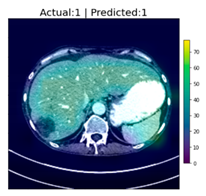

After reaching an accuracy of 95.89%, the training was stopped, and the Grad-CAM method was applied for each of the test images, including those that were falsely classified. The following figure, Figure 6, shows some of the CT images with their associated heat-maps overlaid. In the legends of the figures, “Actual” shows the label for DeepLesion, and “Predicted” shows the output of the CNN classifier.

Figure 6.

CT images with Grad-CAM-generated heat-maps overlaid.

A qualified clinical radiologist from the Center of Acute and Critical Imaging in the Chang Gung Memorial Hospital at Linkou, located in Taoyuan, Taiwan, was consulted for this investigation. He was shown the original CT images in the test set and those same images with their associated heat-maps overlaid. Unfortunately, because of time and other constraints, responses for only 16 images of all the images that were presented to the clinician were received. The following table, Table 3, lists the DeepLesion labels plus the diagnoses from the clinician. The first column is simply an arbitrary number assigned to the image; the second column contains the translucent version of the heat-map overlaying the original image. The third and fourth columns show the DeepLesion labels and the CNN classification results on whether the image contains tumor(s). The fifth column contains the trained radiologist’s diagnosis based on each image. The last column shows the subjective evaluation of the radiologist of the helpfulness of the Grad-CAM-generated heat-map in reaching the diagnosis.

Table 3.

Grad-CAM heat-map-overlaid CT images with respective labels and diagnoses.

For these 16 images, the radiologist’s diagnoses agreed with the DeepLesion labels 12 times and agreed with the CNN results 12 times, though CNN the results differ from the labels in two cases. In these two cases, the radiologist agreed with the DeepLesion labels once and with the CNN results once. In the case where the radiologist agreed with the CNN result, he found the heat-map to be helpful. In the case where the agreement was with the DeepLesion label, the heat-map was considered less helpful. This observation may imply that presenting the heat-maps in addition to the AI-based diagnoses may help physicians in reducing false diagnoses and may help increase the rate of acceptance for AI-based results in the medical community. In addition, for all 16 images, the helpfulness to the radiologist of the Grad-CAM-generated heat-maps ranged from somewhat helpful to really helpful. In no case was a Grad-CAM heat-map considered not helpful at all. From the information contained in the table above, of the clinician’s 16 diagnoses, three of them differ from the DeepLesion labels, i.e., images 6, 11 and 14. In the case of image number 6, where the DeepLesion label indicated no tumor, the clinician diagnosed the opposite, which was in agreement with the CNN result. In this case, the radiologist found that the heat-map was helpful. In the case of image number 11, the clinician diagnosed that what appeared to be tumor(s) is actually cyst(s). The Grad-CAM-generated heat-map for image number 11 was deemed only somewhat helpful. Finally, in the case of image number 14, where the DeepLesion label also indicates that the image does contain a tumor, the clinician diagnosed that there is no tumor, but an inflammation of the biliary tract; in this case, the Grad-CAM heat-map was again deemed somewhat helpful. Based on these three cases, and assuming that the clinician’s diagnoses are correct, it is probable that the Grad-CAM heat-maps can be more helpful in the case of a false negative diagnosis than a false positive diagnosis. Though there appears to be no literature discussing the incorrect labeling of DeepLesion, there are studies indicating that the labels in DeepLesion are incomplete [21].

There is a single case among the 16 images, image 15, where the CNN classifier mis-classified. The image contained no tumor, as DeepLesion labeled and was verified by the clinician, but the classifier generated a false positive. The clinician further clarified that the image did contain cyst(s), but not a tumor, which may be the reason for the false classification. The false prediction may be an indication that the classifier was not trained sufficiently to differentiate between cysts and tumors, as the DeepLesion database did not label cysts. However, the Grad-CAM heat-map was somewhat helpful by pointing out the region(s) where the classifier thought tumors may exist.